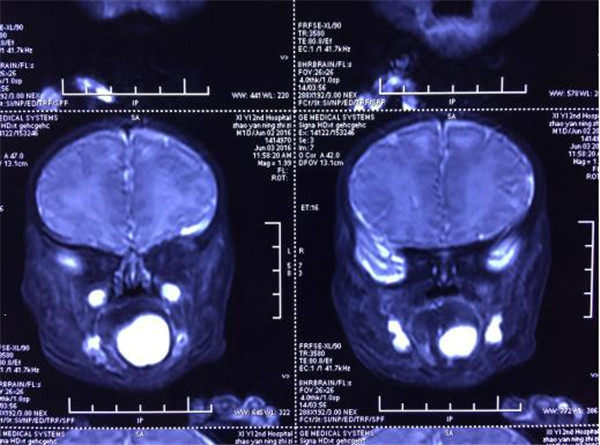

“可乐”入院第1天就在耳鼻喉科协助下抽出囊液7ml,暂时缓解孩子可能随时出现的呼吸问题。孩子情况特殊,病情紧急,上报医院后在医务科组织下,进行了包括小儿外科李鹏副主任、放射科李润民教授、麻醉科李伟教授、耳鼻喉科任晓勇主任、新生儿王惠萍副主任以及西安交通大学口腔医院颌面外科李锦峰主任等多医院、多科室共同会诊后,一致认为该患儿如不进行手术治疗,可能无法生存,但患儿年龄小、囊肿如此巨大,舌底血管丰富、神经丰富,手术风险极大,可能手术中出血直接引发窒息而导致死亡,经过周密研讨,做好术前、术中、术后等应急预案,在告知患儿家属会诊意见后,家属十分谅解手术风险,积极配合治疗。

6月7日早晨8:30分,新生儿舌下巨大囊肿手术在交大二院手术室正式开始。经过麻醉科韩新生教授以及李伟教授麻醉,李锦峰主任以及小儿外科李鹏教授主刀,耳鼻喉科任晓勇主任以及新生儿科保驾护航,经过麻醉,舌下腺分离,保护舌下神经以及保护颌下腺导管,最终成功将巨大的舌下囊肿切除,手术历时1小时,术中无出血,转入新生儿病区NICU监护,“可乐”迎来了他新的生命,患儿最终得到成功救治。目前“可乐”已经可以每次吃奶30ml,近期准备出院。

巨大舌下腺囊肿在新生儿时期发病罕见,巨大舌下腺囊肿出生即可引起呼吸困难窒息,目前国内没有成形的新生儿舌下腺囊肿的救治方案,仅报道一例舌下腺的抽吸。孩子口腔暴露面积小,操作难度大,麻醉中窒息的风险较高,麻醉以及术中出现的任何一点问题均会导致患儿术中出现意外,我院耳鼻喉科做好随时气管切开的准备为手术的顺利进行做好后勤保障,手术后的管理对术后的恢复至关重要,气道以及伤口的管理,口腔分泌物的处理,对新生儿病区的医护人员的技术提出了严峻的挑战。为了预防随时可能出现的舌根水肿以及舌后坠引发的窒息,新生儿病区医护做好相关的应急预案,为患儿手术后的痊愈做好了后续的保障工作。